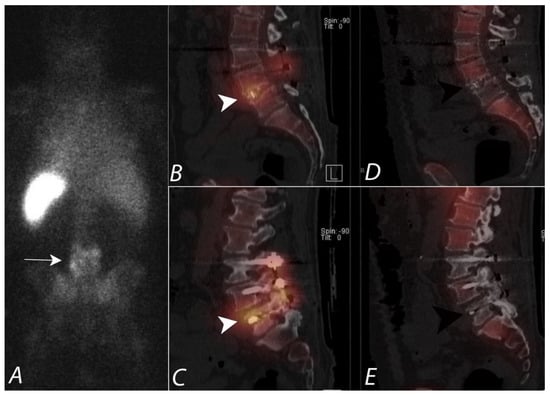

4. Evaluation of Pain of Spinal Origin

- Ryan, P.J.; Evans, P.A.; Gibson, T.; Fogelman, I. Chronic low back pain: Comparison of bone SPECT with and radiograph and CT. Radiology 1992, 182, 849–854. [Google Scholar] [CrossRef]

- Dolan, A.L.; Ryan, P.J.; Arden, N.K.; Stratton, R.; Wedley, J.R.; Hamann, W.; Fogelman, I.; Gibson, T. The value of SPECT scans in identifying back pain likely and to benefit from facet joint injection. Br. J. Rheumatol. 1996, 35, 1269–1273. [Google Scholar] [CrossRef] [PubMed]

- Pneumaticos, S.G.; Hipp, J.A.; Moore, W.H.; Esses, S.I. Low back pain: Prediction of short-term outcome of facet joint injection with bone scintigraphy. Radiology 2006, 238, 693–698. [Google Scholar] [CrossRef] [PubMed]

- Holder, L.E.; Asdourian, P.L.; Links, J.M.; Sexton, C.C. Planar and high-resolution SPECT and high resolution SPECT bone imaging in the diagnosis of facet syndrome. J. Nucl. Med. 1995, 36, 37–44. [Google Scholar] [PubMed]